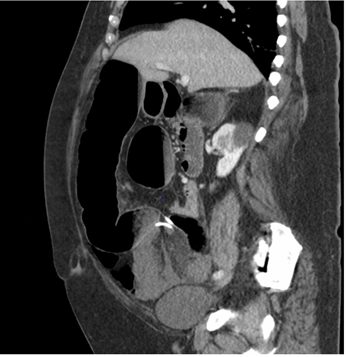

A 64-year-old male with a past medical history of diabetes, morbid obesity (BMI 44), prior surgical history of LAGB placement unknown years before, resulting in a reported 100 pound weight loss, presented to the emergency department with three days of abdominal pain. He reported his pain worsened over that timeframe with associated nausea. He denied any bowel function in the form of flatus or bowel movement. He was not in acute distress. Abdominal exam was pertinent for diffuse tenderness with rebound and guarding. Lab values were pertinent for a leukocytosis of 19, neutrophils of 92.7, hemoglobin of 16.8, platelets 499. Basic metabolic panel included glucose 315, BUN 22, Creatinine 1.2, Sodium 136, Potassium 3.7, Chloride 102, CO2 15, Anion gap 19, Lactate 4.1. His venous blood gas revealed a pH 7.182, pCO2 61.8, pO2 25, bicarbonate 23.7, and base excess -5.6. A CT scan of the abdomen and pelvis identified a large bowel obstruction at the level of the mid sigmoid colon with the LAGB catheter looped along the sigmoid mesentery in the pelvic inlet, as depicted in Figures 1 and 2. After resuscitation with 2 liters of crystalloid the patient was transferred urgently to the operating room for exploratory laparotomy. Intra-operatively marked dilation of the entire intestinal tract and a large loop of sigmoid colon was found to be strangulated by several loops of the LAGB catheter that wrapped along the rectosigmoid mesentery. The large bowel was decompressed proximally and distally with needle catheter suction. The enterotomies were closed with a figure of eight 3-0 polysorb suture. The sigmoid colon appeared dark and hemorrhagic as well. After extensive lysis of adhesions the catheter was excised and trimmed flush with the LAGB reservoir at the upper abdomen. The sigmoid colon was observed as it regained a viable color after a few minutes. In addition the mesenteric pulse was palpable. The abdomen was closed with a running 0 Maxon suture and the patient tolerated the procedure well. Post-operatively the patient progressed uneventfully. His discharge was delayed due to newly diagnosed hypertension, however once optimized he was discharged on post-operative day 7 (Figures 1) (Figures 2).

Figure 1 Axial Computed Tomography (CT) of Abdomen/Pelvis Demonstrating Acute Large Bowel Obstruction due to LAGB Catheter.